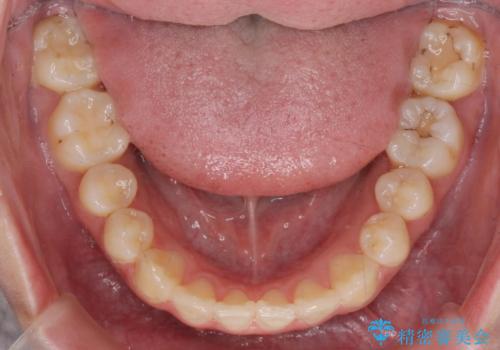

- 前歯の角度 奥歯の噛み合わせの改善をするために、矯正治療を希望され来院されました。

右側奥歯は上顎が相対的に前方に位置し(上顎前突)、そのため前歯の角度も突き出たようになり出っ歯のように見える状態でした。

マイクロインプラントを用いて、上顎奥歯を後方に移動させることで噛み合わせ・前歯の角度を改善していきます。